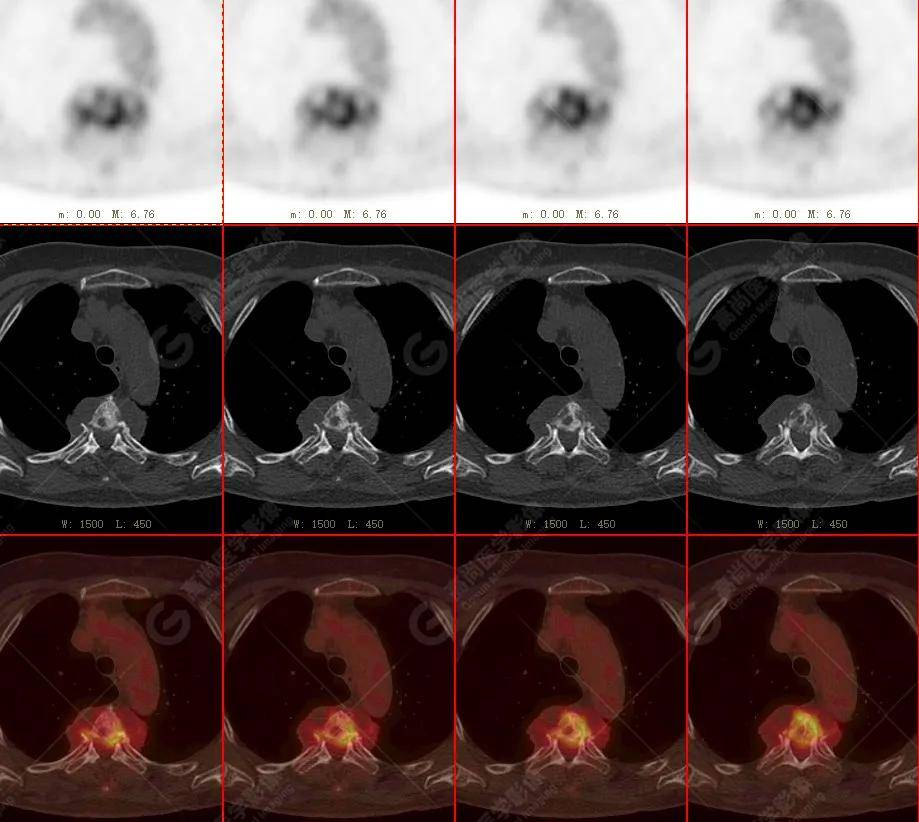

【高尚病例】18f-fdg pet/ct显像应用于骨结核

图片尺寸921x892